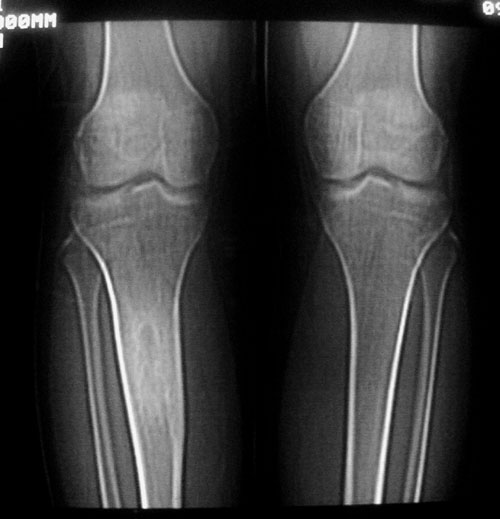

以下是引用卜一在2007-11-12 5:56:00的发言:[br]胫骨中上段骨内外膜增生,骨质硬化,部分骨皮质增厚,髓腔高度变窄,界限不清。多考虑:1 慢性低毒性感染。2 不除外骨纤维异常增殖症!